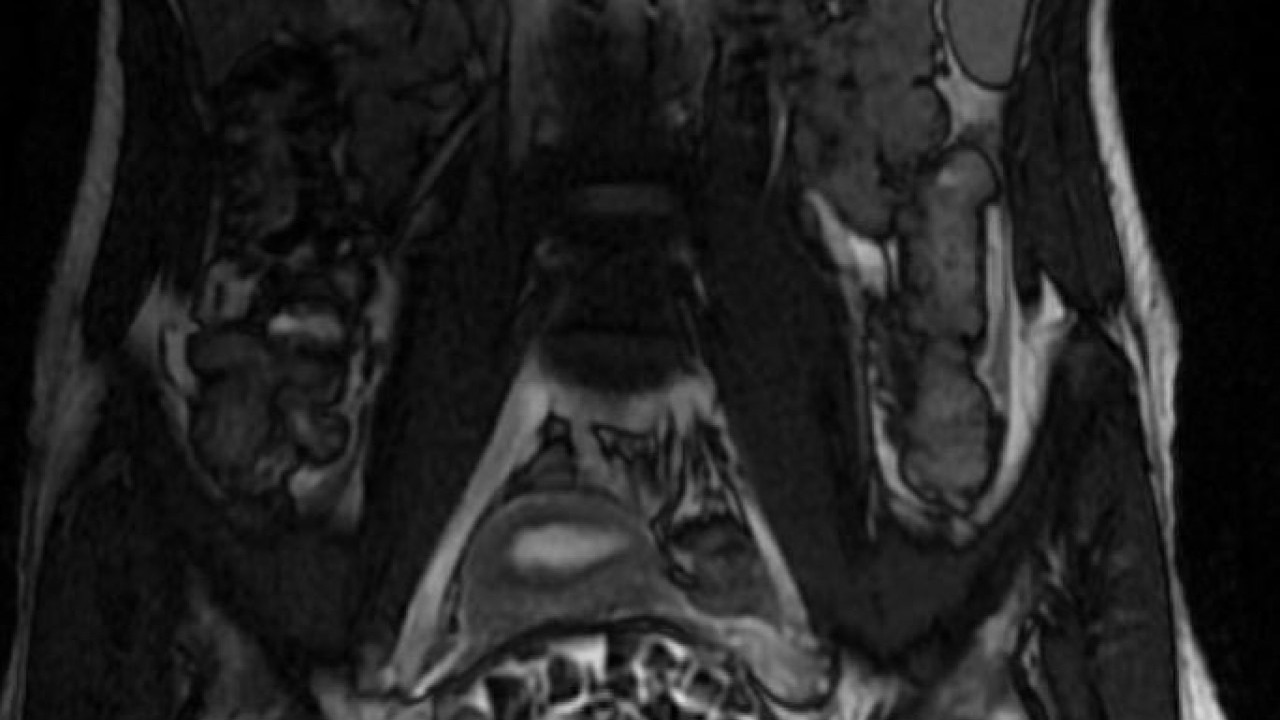

"287 adet taş çıkardık, literatürde çok nadir görülen bir olay" Hastasının durumuna yönelik konuşan Üroloji Uzmanı Doç. Dr. Erkan Erkan, "Hastamızın 2004 yılında doğduğunu ardından doğar doğmaz ekstrofi vezika dediğimiz 50 binde bir görülen bir anomaliden dolayı art arda ameliyatlar geçirdiğini öğrendik. 10 yaşında yine bir ameliyat geçirmişti, gerekli görüntüleme ve tetkiklerimizi yaptırdık. Normalde mesanesinin olması gereken yerin hemen arka kısmında taşlarla dolu bir kese olduğunu gördük, bunun üzerine ek görüntülemeler; MR çektirdik. Hastamız çelişkili açıklamalar almıştı, kendi radyolojik kliniğimiz ve edindiğimiz konsültasyonlarda taşların mesanede değil vajinal boşlukta oluştuğunu düşündük, bir planlama yaptık. Kadın doğum hocamızın da çabasıyla taşları tamamen temizledik ardından ileride normal bir hayat sürmesi bakımından oraya plastik cerrahi yaptık. 287 adet taş çıkardık, pratikte gerçekten görünce çok şaşırdık çünkü bu aynı zamanda literatürde çok nadir görülen bir olay. Biz ameliyata hazırlanırken de teorik olarak biraz araştırdık. Literatürde gördüğümüz kadarıyla buna benzer bu tanıma uyan bir vaka vardı. Literatürde sanırım yayınlanmış 2’nci vaka olacak. Farkındalık çok önemli, bilinçli bir hastamız vardı. Doğumsal anomaliyle doğan çocuklarımızda ileride bunlara bağlı bazı sıkıntılar çıkabileceğinin öngörülmesi lazım. İlgili tedavilerini alsalar bile düzenli takiplere gelmeleri gerekiyor. İleride eğer dikkat etmezse ki zannetmiyorum, tekrarlayabilir. Bu rahatsızlık ekstrofi vezikal epispadias durumu çok nadir bir durum" dedi.

"Tüm vajenin taşlarla dolu olduğunu gördük" Genç kızın uzun süredir devam eden karın ağrısı olduğunu söyleyerek sözlerine başlayan Jinekolojik Onkoloji Uzmanı Op. Dr. Emin Erhan Dönmez, "Mesane taşları olduğu düşünülerek daha büyük bir hastaneye refere edilmiş. Aramızda mini bir konsey yaparak muayene ettik. Vajen bir hazne görevi görerek orada durağan bir idrar, uzun süre beklediği için idrar içindeki minerallerde çökerek taşlar oluşmuş. Mesanedeki idrarın vajene akmış olabileceği ve vajende göllenen idrar nedeniyle taşların burada oluşacağını düşündük, ameliyatımızı planladık. Ameliyata tanı amaçlı girmiştik, sistoskopi (Mesane gibi idrar yollarını kapsayan kısımlardaki rahatsızlıkların teşhis ve tedavisinde kullanılan endoskopik bir yöntem) dediğimiz ameliyatı Erkan Hocam ile birlikte gerçekleştirdik. Önce mesaneyi bir görüntüledik, mesane tabanına yaklaşık 2-3 cm’lik bir alandan vajene fistülize olduğunu gördük. Mesaneden vajene geçtiğimiz esnada tüm vajenin taşlarla dolu olduğunu gördük.

Tanı amacıyla girdiğimiz ameliyatta her şey de olağan gittiği için tedaviye geçtik. Taşların çıkabileceği kadar bir genişlik sağladık. Daha sonra yaklaşık en büyüğü 2,5 cm boyutlarında olan, irili ufaklı 287 tane taşı ameliyat esnasında çıkarmış olduk. Taşların tekrarlamaması için idrarın göllenmemesi, en azından dışarıya rahatça boşalabilmesi için vajinal rekonstrüksiyonu sağladık. Ameliyatta da herhangi bir problem yaşamadık. Literatürü Erkan Hocam ile birlikte değerlendirmiştik. Primer olarak vajende birikmiş olan bu kadar çok sayıda taşla ilgili bir makale görmedik, rastlamadık" dedi.